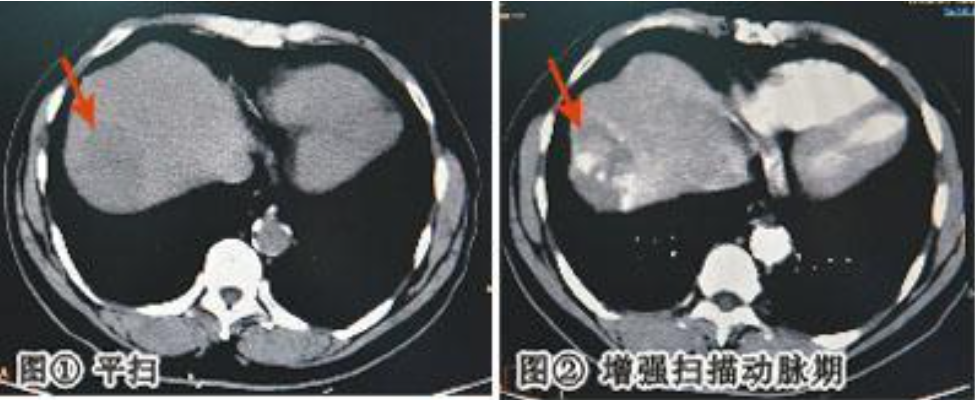

CT 增强是在 CT 平扫 的基础上,通过静脉注射含碘的造影剂,让血管、脏器、肿瘤等组织在影像上显示更清晰的一种检查方式。

✅ 动态观察:动脉期、静脉期、延迟期多阶段成像,帮助医生全面分析